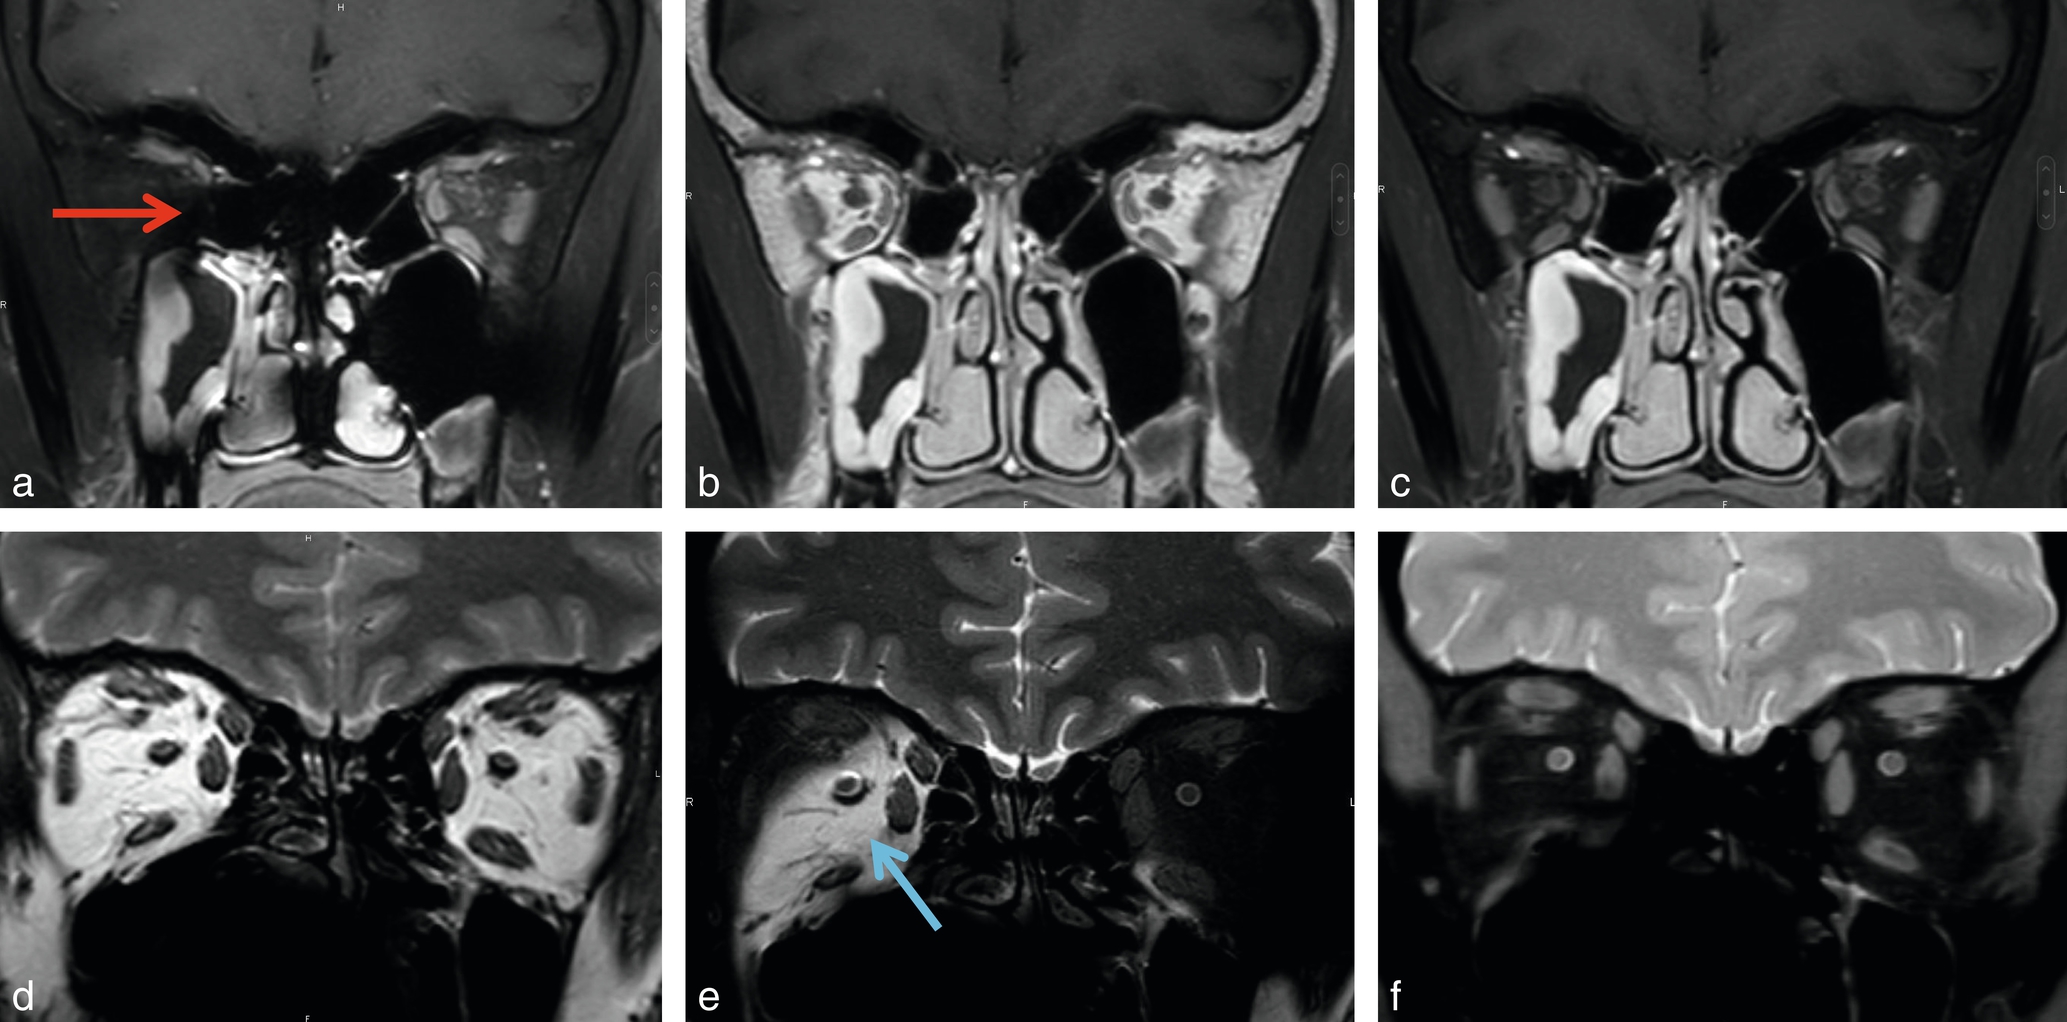

La graisse orbitaire ou de la base du crâne, en hypersignal T1 et T2, aide à détecter de nombreux processus pathologiques en hyposignal. En revanche, si la lésion est inflammatoire (hypersignal T2) ou rehaussée (hypersignal T1), elle disparaît dans la graisse. Pour mieux la visualiser, on utilise la suppression du signal de la graisse (ou FAT-SAT) que l'on ajoute à la séquence T2 ou T1 injectée et la graisse devient noire. De plus en plus, on utilise une séquence de type Dixon, qui en une acquisition donne à la fois un T1 ou un T2 et le même avec FAT-SAT calculée, celle-ci étant généralement moins sensible aux artefacts que la FAT-SAT standard (fig. 2-26

Fig. 2-26

Orbites normales, coupes coronales.Comparaison FAT-SAT et Dixon en T1 injecté: T1 FAT-SAT(a), Dixon sans FAT-SAT(b), Dixon avec FAT-SAT calculée(c) et T2: SE(d), FAT-SAT(e), Dixon avec FAT-SAT calculée(f). Artefacts (flèche rouge) et mauvaise saturation de la graisse qui reste blanche (flèche bleue).

) [5,6].